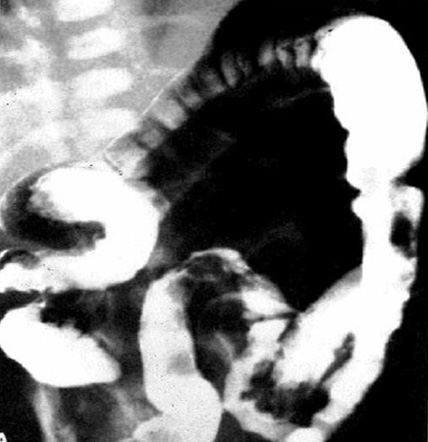

A contrast enema performed with water-soluble contrast material is the most valuable imaging test for Hirschsprung's disease. A contrast enema is recommended if the clinical evaluation is suspicious for Hirschsprung's disease or if there are signs of distal obstruction on x-ray. A rectosigmoid ratio (maximum diameter of the rectum divided by maximum diameter of the sigmoid colon during contrast enema) of <1 is highly suggestive of Hirschsprung's disease. Other suggestive findings include retained contrast at >24 hours, mucosal irregularity, or microcolon.[48] A transition zone may be seen on contrast enema but this may be less obvious in neonates.[49] A transition zone on contrast enema can help with surgical planning, but it should be noted that the radiographic transition zone may not correlate with the histological transition zone.[50] Contrast enema may demonstrate mucosal irregularity in the aganglionic distal colon and may show a transition zone between smaller calibre aganglionic distal colon and dilated proximal ganglionic colon.[Figure caption and citation for the preceding image starts]: Barium enema performed in a newborn with Hirschsprung's disease. Often, classical changes are not obvious in the neonatal periodCorman ML. Colon and rectal surgery. 5th ed. Philadelphia, PA: Lippincott Williams and Wilkins; 2005:555-603; used with permission [Citation ends].